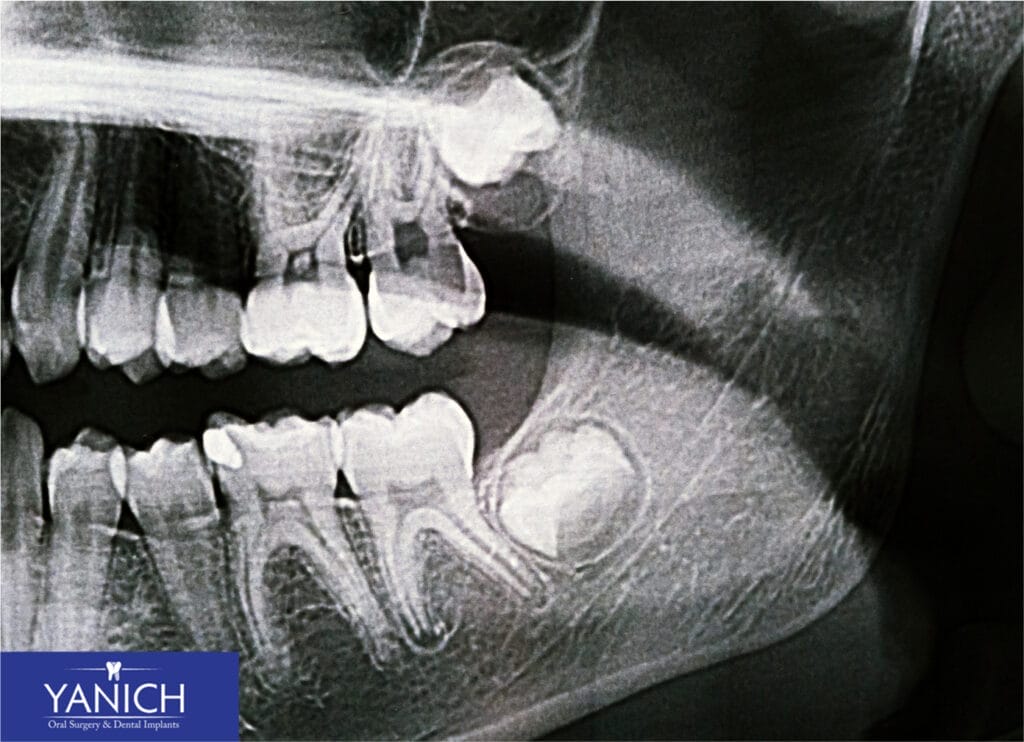

Impacted wisdom teeth—those that don’t have enough room to emerge or develop normally—almost always require removal. These teeth might be trapped beneath the gum line, partially erupted, or emerging at an angle.

Impacted wisdom teeth can lead to various problems:

- They can push against other teeth, causing pain and misalignment

- They create spaces that trap food and bacteria, leading to decay

- They can develop cysts that may damage the jawbone and nearby teeth

The tricky part about impacted wisdom teeth is that they might not cause noticeable symptoms right away. That’s why regular dental check-ups with X-rays are so important—they allow us to monitor how your wisdom teeth are developing before they cause problems.